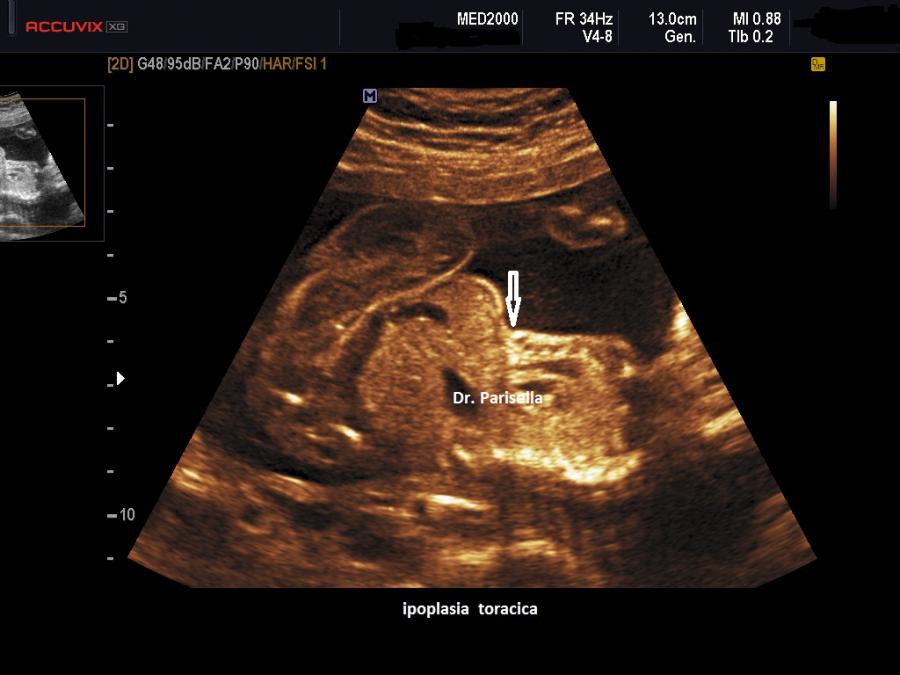

Osteocondrodisplasia di Blomstrand OMIM 215045

E' una displasia scheletrica autosomica recessiva caratterizzata da grave accorciamento di tutti i segmenti ossei degli arti, torace stretto con coste corte, protrusione della lingua (glossoptosi) dovuta alla cavità orale piccola, ipoplasia dello splacnocranio. Spesso si associa polidramnios.